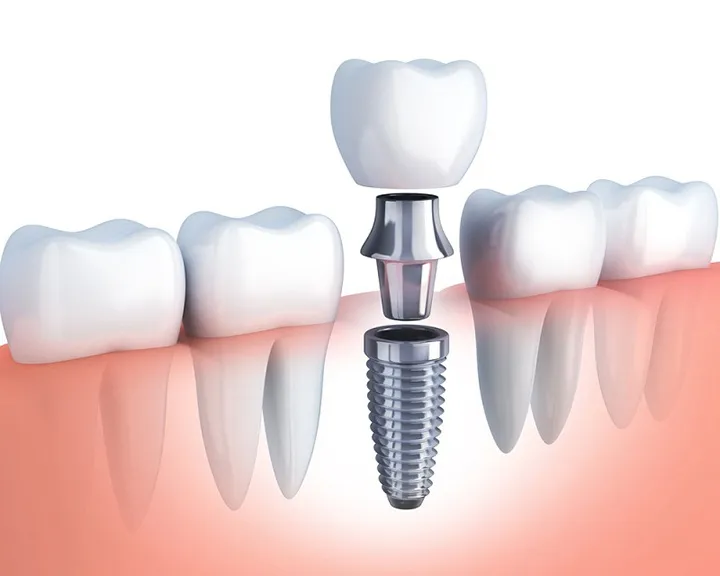

- Phục hồi Xương: Trong những trường hợp viêm tủy xương hàm mạn tính gây tiêu xương nặng, bác sĩ có thể cần thực hiện ghép xương sau khi ổ nhiễm trùng đã sạch hoàn toàn, nhằm phục hồi thể tích và độ vững chắc của xương hàm.